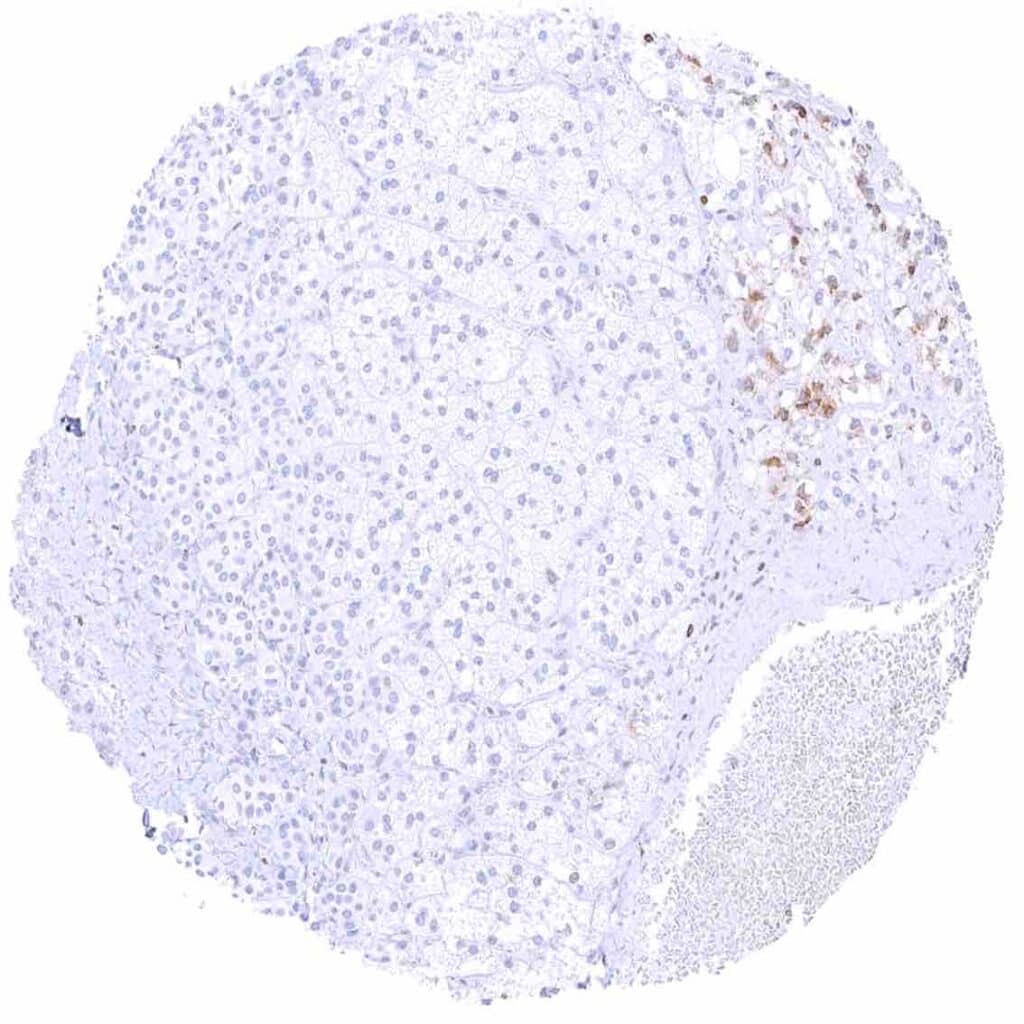

Lymph node – Strong bcl-2 positivity of a large fraction of lymphocytic cells in the interfollicular area and around germinal centres while almost all cells in germinal centres are bcl-2 negative.